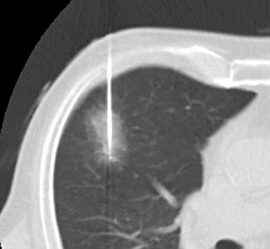

悪性腫瘍ラジオ波焼灼療法(肺)

◆経皮的針生検 (肺・乳房・肝・腎・骨)